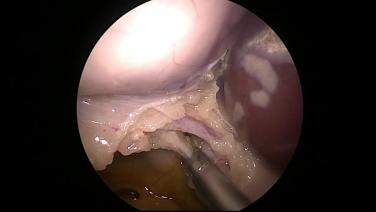

Laparoscopic Cholecystectomy - Identify Triangle of Calot

Laparoscopic Cholecystectomy - Identify & Ligate Cystic Duct

Laparoscopic Cholecystectomy - Identify & Ligate Cystic Artery